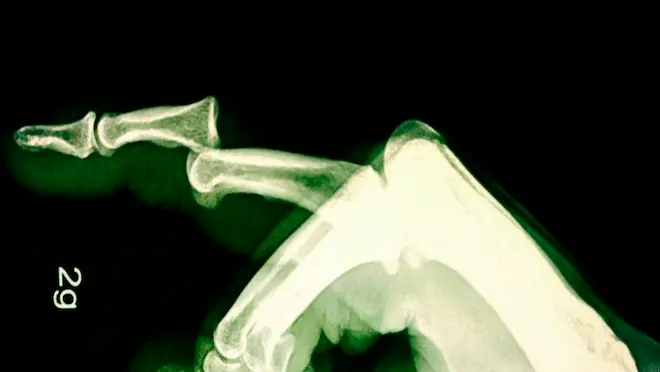

Jeu Twitter #Jejoueaudocteur : une luxation de l'index en images

"Voilà une belle luxation de l'index...". Tirer dessus n'a pas suffi, il a fallu aller au bloc....